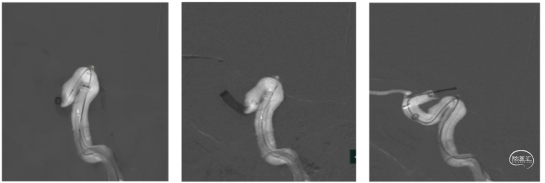

泥鳅导丝携带125cm多功能导管导引088抽吸导管8F 115cm置于颈总动脉,在泥鳅导丝导引下可单独上至海绵窦段。下图1、2

远端通路导管6F 130cm导引心玮吞川抽吸导管到达血栓近端进行第一次抽吸后海绵窦后膝显影,远端仍闭塞,血管迂曲严重。下图3

微导丝、微导管导引6F 130cm远端通路导管越过海绵窦后膝,并导引心玮吞川抽吸导管深入残余血栓进行第二次抽吸,眼动脉显影,眼段以远仍闭塞。

远端通路导管6F 130cm在微导丝及微导管导引下越过虹吸弯,并导引088抽吸导管到达血栓近端,应用其大口径及强负压对血栓进行第三次抽吸,直接原位抽出血栓,血管完全再通,无血栓逃逸及残留。